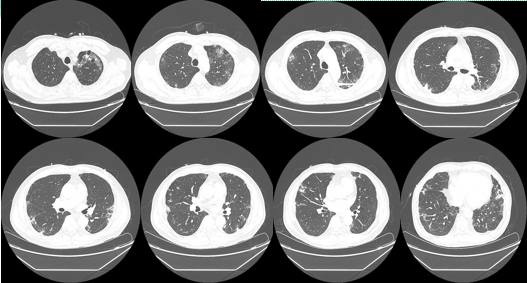

胸部CT:双肺多发斑片影及条状影,间质性改变;主动脉及冠脉钙化,详见图1。

图1 胸部CT影像学表现

本例患者为老年男性,间断出现胸闷,咳嗽,咳痰,伴心悸,间断发热,体温最高38.0℃,入院查白细胞、中性粒细胞占比均正常,CRP、血沉及PCT等升高,胸部CT示:双肺多发斑片影及条状影,间质性改变;主动脉及冠脉钙化,以“胸闷原因待查”收入我院。

后进一步实验室检查示抗核抗体ANA:阳性(核均质型,1:3200)抗Ro52抗体:阳性(>400RU/mL),结合患者间断咳嗽、咳痰,活动后胸闷伴有发热,口干等症状;胸部CT示双肺外带弥漫性改变,以磨玻璃结节、实变为主等影像学改变;唾液腺病理可见淋巴细胞灶状浸润等,经验性抗感染治疗效果,最终临床诊断为“干燥综合征”。